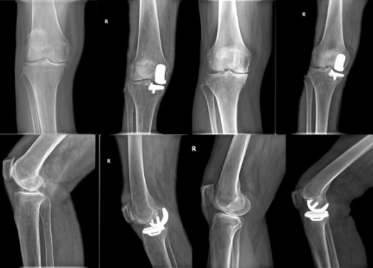

“以前听说膝骨关节炎需要手术做全膝关节置换,要不就长期吃药,没想到还能做微创,效果好还省了不少钱”患者彭女士(化名)说。